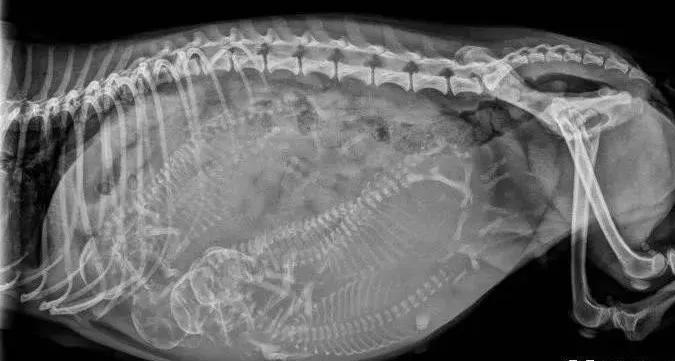

6、配种后的3~4周后可以去医院进行B超检查,即可确诊是否怀孕,并且看出胎儿的大致数量和位置。配种5-6周后可以进行X光照影,确认胎儿的具体数量。确诊怀孕后,应每两周到医院进行一次产检,检查胎儿发育状况,以及估算预产期。